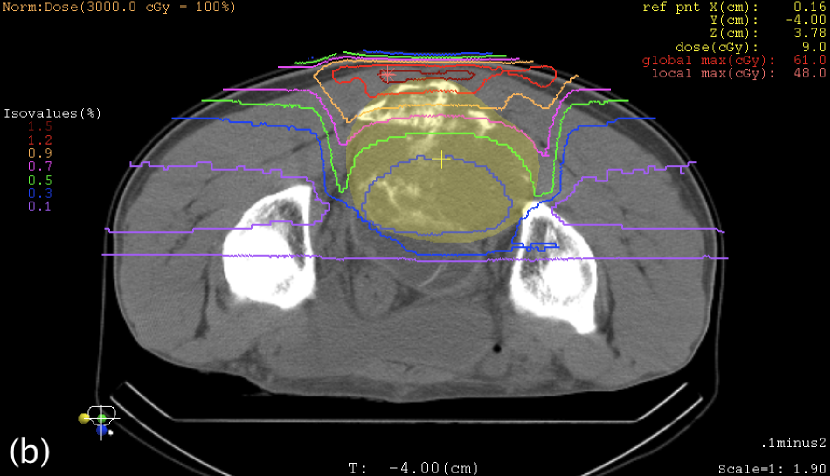

III.3 Case study

Table 3 shows the maximum WE thicknesses of the range compensators. Except for the posterior beam in the sacrum case, range compensation was large as it had been expected for oblique-incident beams. Figures 4 and 5 show the plan dose distributions, in which the reduction of clinical dose was 0.30% at the isocenter in the sacrum case, 0.75% at the isocenter in the nose-and-sinus case, and mostly within 1% in these targets. In the nose-and-sinus case, the dose reduction greater than 2% occurred only in the air that happened to be included in the dose-calculation volume. Relatively speaking, the dose reduction was greater in the posterior part of the sacrum target and in the anterior-left (away from nose) part of the nose-and-sinus target, which was caused by locally shallower target depth and hence larger range compensation in the fields.